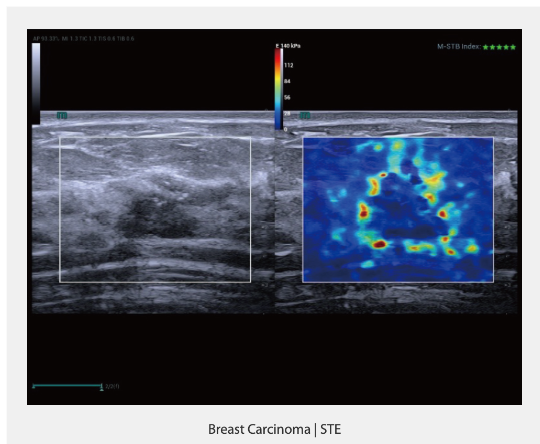

Sound Touch Elastography (STE)

STE расширяет возможности визуализации. С использованием множества инструментов контроля качества и интеллектуальных технологий она интуитивно и количественно оценивает жесткость тканей, что делает ее высокоэффективной для диагностики фиброза печени и опухолей молочной железы.

-

Высокая производительность визуализации

-

Множество инструментов контроля качества

-

Интеллектуальные инструменты (Smart tools)

- Карцинома молочной железы